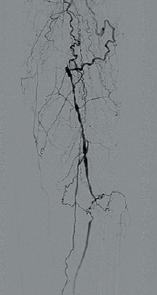

骨搬运手术后,产生大量的新生血管网

搬运后血管网密集